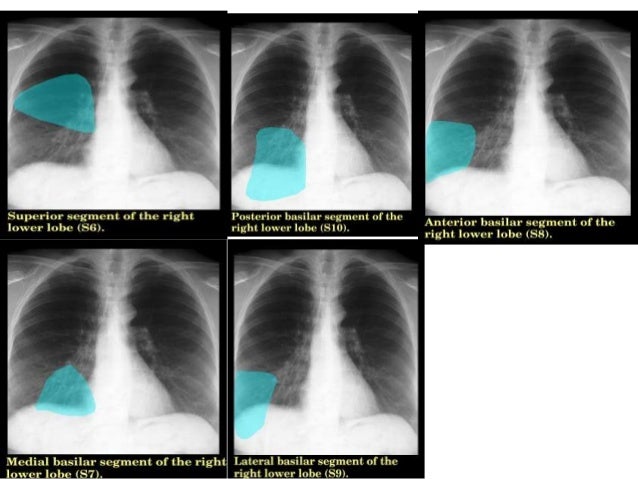

21+ Lung Segments Anatomy. Knowledge of the anatomy of the bronchopulmonary segments is essential for precise interpretations of diagnostic images of the lungs and for surgical. Gross anatomy the trachea divides at the carina forming the left.

Each segment is filled with many small bronchioles, which extend throughout the lung tissue and branch into terminal bronchioles. Figure 2 is a guide to the. Of the segmented ct lung phantom.